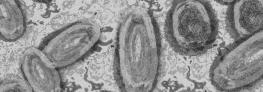

Les orthopoxvirus constituent une famille de virus à laquelle appartiennent la variole, mais aussi la vaccine et le mpox (nouveau nom du virus monkeypox).

Aujourd’hui éradiquée grâce à la vaccination, la variole a été pendant plusieurs siècles une des premières causes de mortalité dans le monde. Elle se transmet par contact physique direct ou par l’échange d’objets contaminés. En dehors de la variole et du mpox, les autres orthopoxvirus transmissibles à l’homme (vaccine, buffalowpoxcamelpox...) sont considérés comme moins virulents.